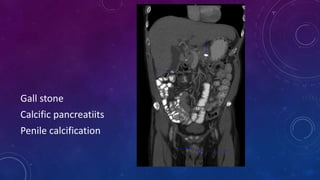

SPOT 3 ORGANS

WITH

CALCIFICATIONS

Gall stone

Calcific pancreatiits

Penile calcification

• #73 Gall stone Calcific pancreatiits Penile calcification